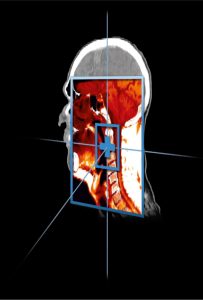

Deforme Edilebilir MR/CT | Sonuçların Doğruluğu Güvence Altındadır!

Çoklu modaliteli deforme edilebilir hizalama, çözmesi zor bir problemdir. Reg Reveal aracı icat edilmeden önce daha da zor bir iş, hizalamanın doğru olup olmadığını saptamaktı. Günümüzde Reg Reveal ve Reg Refine sayesinde MIM, CT deforme edilebilir hizalamayı planlarken MR’ın doğruluğundan emin olabilirsiniz.